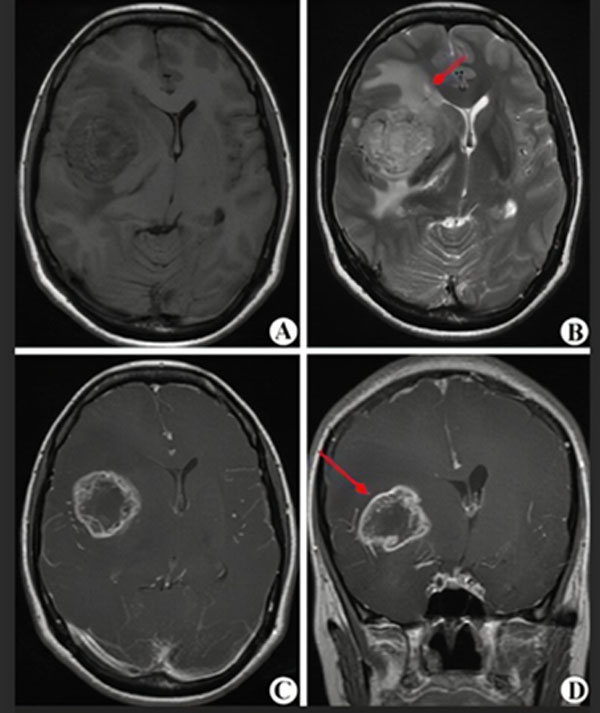

MRI(核磁共振)是一种无创伤的影像学检查,对脑肿瘤敏感性较高,大约1-2天可以拿到结果,是诊断和评估治疗效果的首选。但准确性只有80%-90%,不能作为确诊的最终依据。

(图A-D显示为高级别胶质瘤的核磁表现,红箭头指示肿瘤所在)

胶质瘤最终确诊还要依靠立体定向穿刺或开颅手术等有创操作,取得病变组织,由病理科医生确认病变是否为胶质瘤以及胶质瘤的级别,这一过程大约需要7-10天。